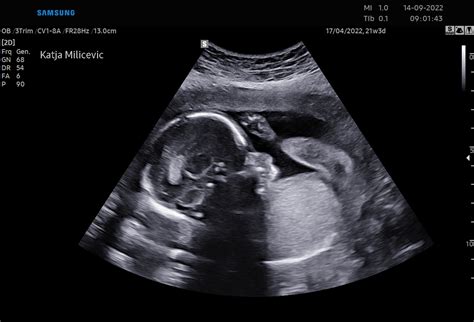

Ultrazvok: Med 11. in 14. tednom nosečnosti se pogosto opravi ultrazvočni pregled nuhalne svetline (NT). Ta neobvezen ultrazvok meri debelino tekočine na zadnji strani otrokovega vratu in pomaga pri ocenjevanju tveganja za kromosomske nepravilnosti, kot je Downov sindrom.